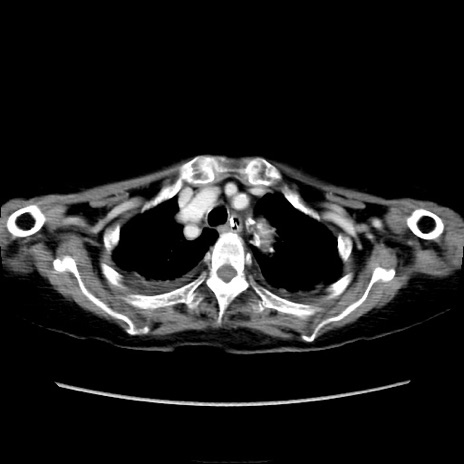

症例40(横断像)

【症例】90歳代女性

【主訴】腹痛・嘔吐

【現病歴】 食欲低下、嘔吐があり昨日他院受診。肺炎と診断され入院となる。入院後より腹部全体に圧痛あり。胃管留置され経過みていたが、症状持続するため、

当院転院となる。

【既往歴】胸椎圧迫骨折、胆石症

【身体所見】腹部:中央に激痛あり、圧痛あり、反跳痛不明

【データ】WBC 17100、CRP 18.82

他院CT